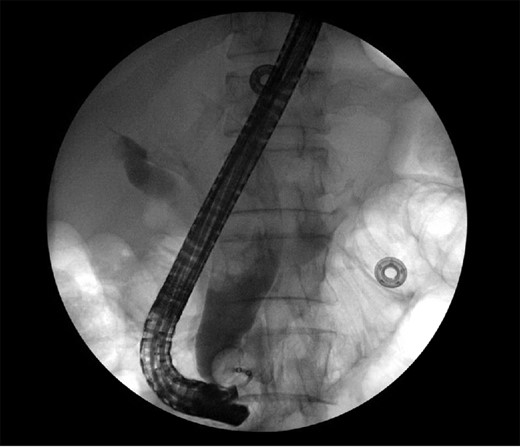

The patient is a 63-year-old Chinese male who presented with lethargy, 10-pound weight loss and painless jaundice for 1 week. Patient had a prior episode of jaundice of unclear etiology 2 years prior treated medically and had just emigrated from China 1 month prior to admission. Patient was febrile to 102.4°F, jaundiced with a total bilirubin of 18.5 mg/dL. Abdominal ultrasound showed intra and extrahepatic bile duct dilation, the distal CBD was dilated to 25 mm. Patient underwent endoscopic retrograde cholangiopancreatography (ERCP), which showed thick yellow mucus and no stones (Fig. 1). A sphincterotomy was performed and a pigtail stent placed. Computed tomography (CT), magnetic resonance imaging and magnetic resonance cholangiopancreaticogram failed to show a pancreatic head mass, distal CBD mass or stones causing obstruction (Fig. 2). Cold forceps biopsy of the papilla, endoscopic ultrasound with fine needle aspiration biopsy (FNAB) of pancreatic head, and CBD brushings were all nondiagnostic. CBD stents occluded two times in 2 weeks’ time secondary to thick mucus, requiring multiple ERCPs with stent exchanges (Fig. 3). After extensive multidisciplinary discussions regarding unclear etiology of distal CBD obstruction and extensive discussion with patient and family, the decision was made to perform a Whipple procedure for diagnosis and definitive treatment. Intraoperatively, choledochoscopy was performed, which showed very thick yellow mucus and frond-like mucosa near the ampulla. Final pathology showed a 2.0 × 1.5 × 0.5 cm3 granular lesion in the distal CBD. There was prominent biliary epithelial proliferation with tubular–papillary architecture and minimal nuclear atypia in association with chronic inflammation, stroma reaction and smooth muscle proliferation. The overall histological change in the distal CBD resembled that of AH seen in gallbladder, likely non-neoplastic change (Figs 4 and 5). At 1 year follow-up, he is doing well and his jaundice has resolved.

Repeat endoscopy 1 week after ERCP with sphincterotomy and stent placement shows thick mucus obstructing CBD.